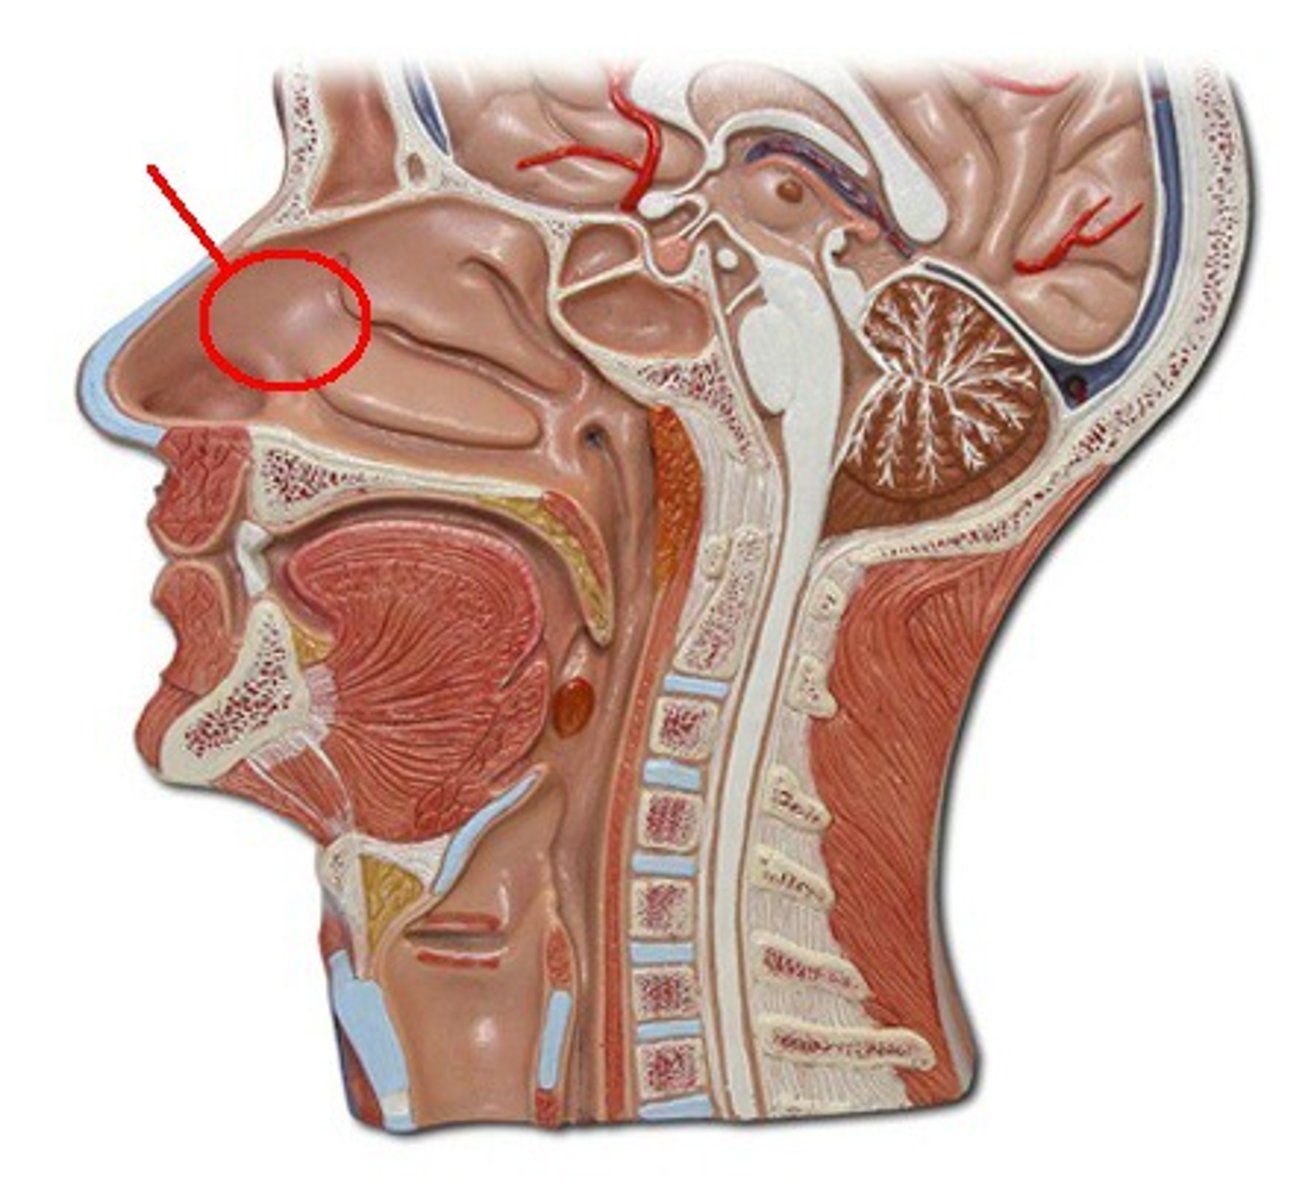

Frankfurt Plane

A horizontal plane that includes the orbitals and external acoustic meatus in anatomical position.